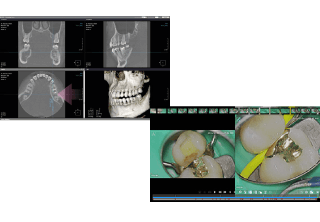

歯をできるだけ残す治療 - 歯科治療では、見落としをなくし可能な限り正確・精密に不安要素を取り除くことが、良好な結果に繋がると考えています。だからこそ当院では、視野を拡大する手術用顕微鏡マイクロスコープ、表面に出ない歯や顎の内部まで映し出す歯科用CT、インプラント埋入を補助するガイドをはじめとした機器を駆使し、治療・診断精度の向上に努めています。

当院では専用のカウンセリングツールやマイクロスコープの録画システムを用い、現在のお口の状態や治療計画、実際行った治療を、写真や動画など目に見える形でお伝えし情報共有することを重視しています。